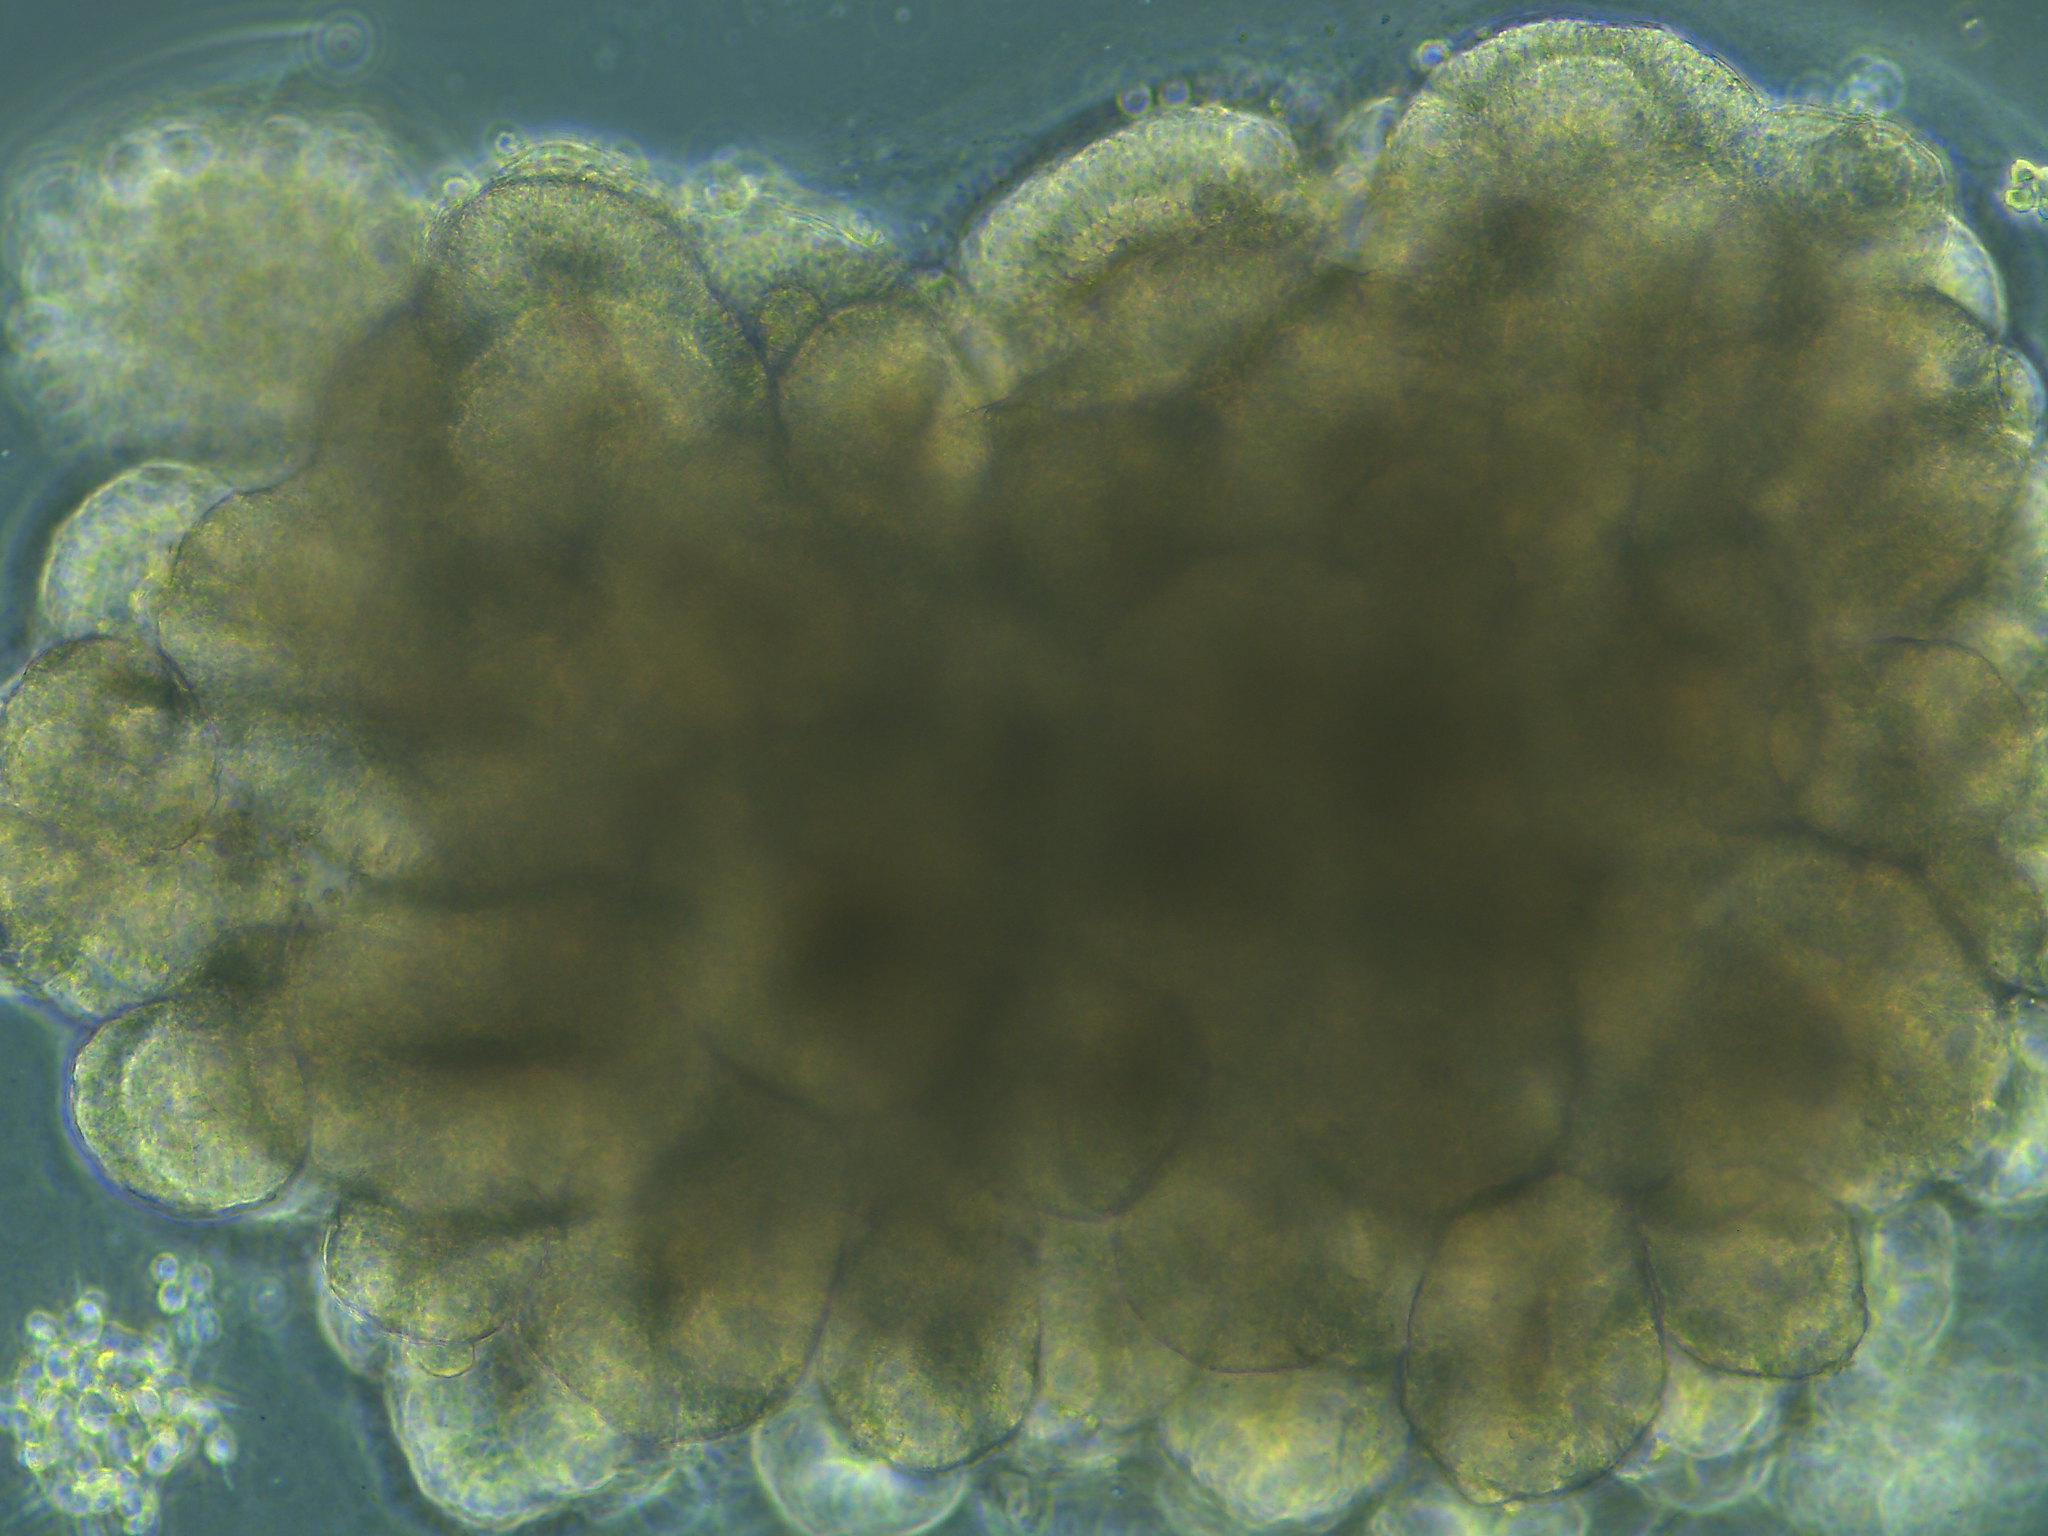

Биология вышла на следующий уровень. Ученые доказали, что стволовые клетки могут самоорганизовываться в сложные 3D-структуры — мозговые органоиды. Это не просто кучка клеток, это миниатюрная, упрощенная модель ткани мозга. Добавьте сюда технологию «орган-на-чипе» (устройства, имитирующие физиологию тела), и вы получите идеальный полигон для экспериментов.

Сегодня органоиды — это рутина фармацевтов. На них тестируют лекарства и изучают болезни. Но активность этих сгустков ткани оставалась хаотичной. До недавнего времени.